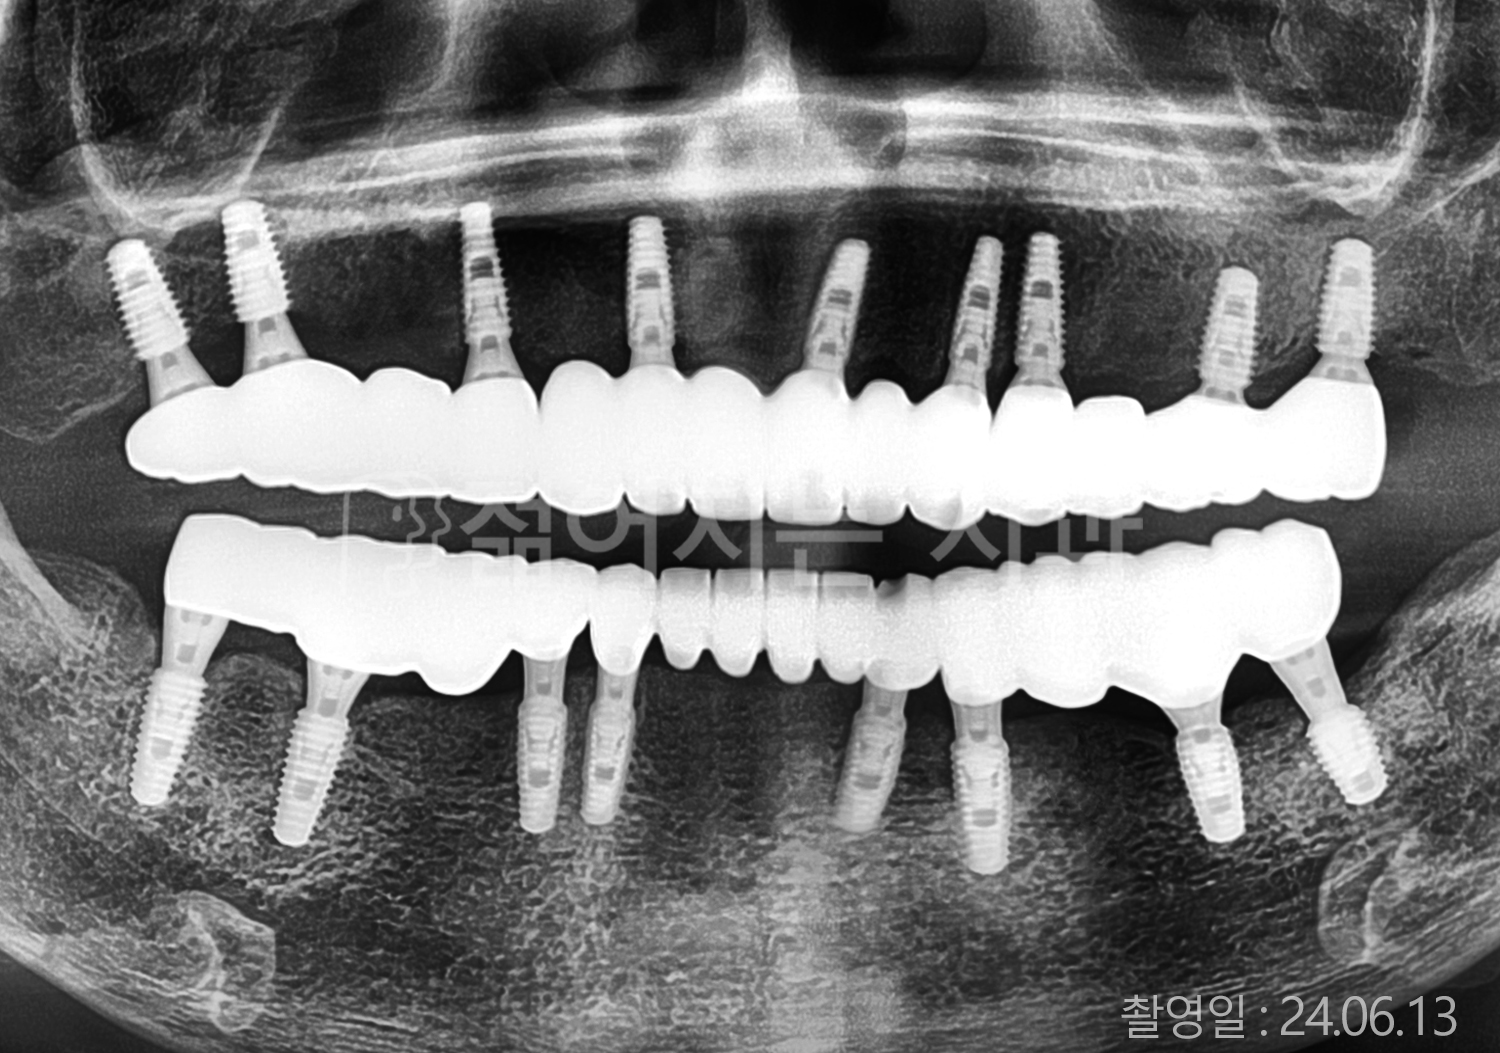

• 70대 고혈압, 고지혈증 전체치아 10개 이상 임플란트

• 60대 당뇨, 간염 전체치아 10개 이상 임플란트

• 80대 골다골증 전체치아 6개 이상 임플란트

• 70대 고혈압, 당뇨 전체치아 10개 이상 임플란트

• 60대 간 질환 전체치아 10개 이상 임플란트

• 60대 전체치아 10개 이상 임플란트

• 70대 전체치아 10개 이상 임플란트

• 50대 전체치아 10개 이상 임플란트

• 60대 고혈압, 고지혈증 전체치아 10개 이상 임플란트

• 40대 고지혈증, 뇌혈관 질환 전체치아 10개 이상 임플란트